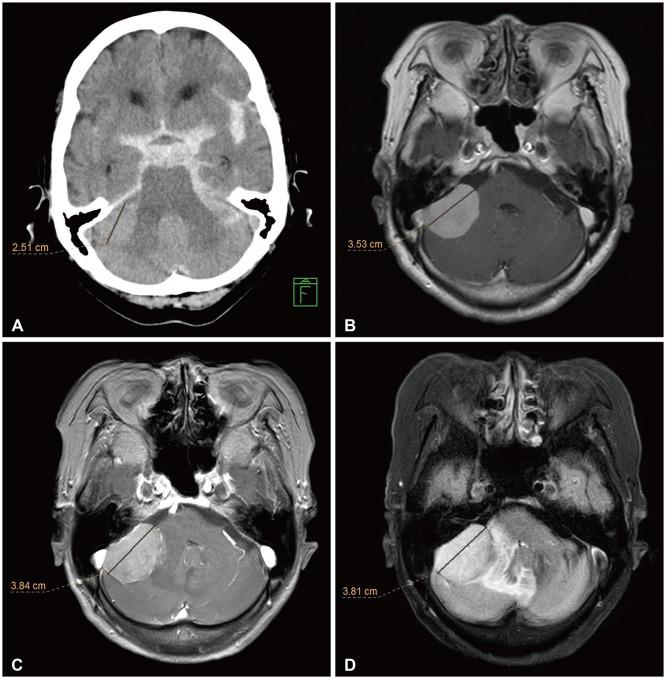

This preliminary study evaluates the safety and efficacy of CyberKnife radiosurgery (CKRS) for large-volume meningiomas (≥10 cm³), where surgical options may be limited due to tumor location or patient health conditions.

We retrospectively analyzed 18 patients with meningiomas treated with CKRS at Gyeongsang National University Hospital between 2010 and 2020. Tumor control and survival rates were evaluated, with follow-up imaging performed regularly.

CKRS achieved a 5-year overall survival rate of 92.3% and a 5-year tumor control rate of 93.8%. Symptomatic peritumoral edema occurred in 61.1% of patients, with 16.7% requiring surgical intervention.